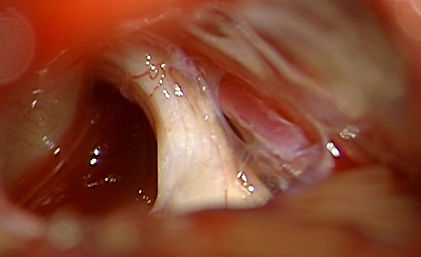

ETV - endoskopiska 3. vēderiņa ventrikulocisternostomija

Izveidota atvere 3. vēderiņa pamatnē okluzīvas hidrocefālijas gadījumā -

smadzeņu šķidrums brīvi pulsē.

Hidrocefālija likvidēta.